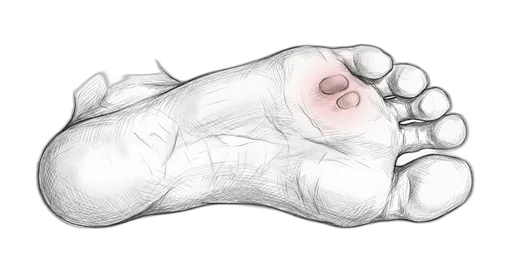

Foot & Ankle Exercise Guide

Choose your condition below to get started with exercises and stretches designed by Dr. Patish.

Pick your condition below, and you'll find your personalized exercise program — with medical illustrations, step-by-step instructions at three intensity levels, and clear guidance on when to call our office. Every protocol here is the same one Dr. Patish prescribes to patients in the clinic.

Forefoot & Toes